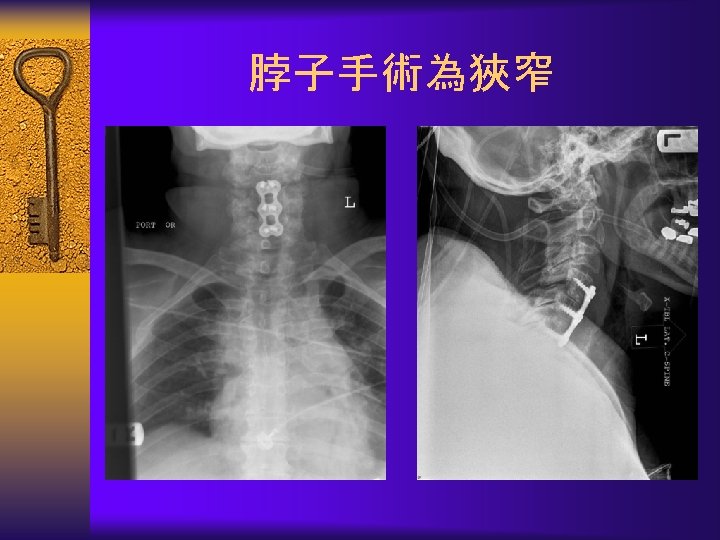

Surgical Treatment-Fusion 融 合 ¨ Instability – Spondylolisthesis – Scoliosis – Severe disc degeneration

Surgical Treatment-Fusion(融 合)